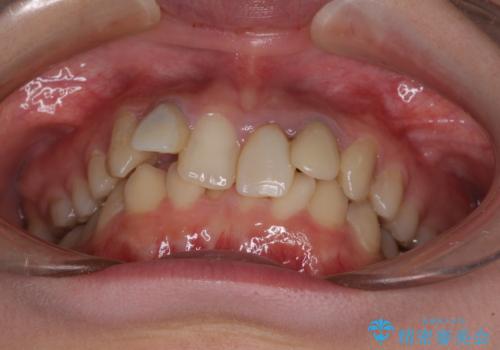

- 前歯のデコボコと、その結果むし歯が進行していることを気にして来院された患者様です。

前歯や奥歯の根管治療を行い、その後上下左右の第一小臼歯4本を抜歯してワイヤー装置にて矯正治療を行うこととしました。

矯正治療後には、根管治療を行った歯をオールセラミッククラウンにて補綴治療を行うこととしました。

治療途中で激務の会社に就職することとなり、なかなか矯正治療に通院することができなくなり、治療期間が想定の2倍近くとなりましたが、無事に満足のいく形で治療を終えることができました。